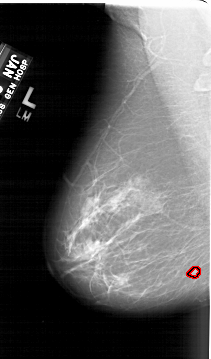

A_1687_1.LEFT_CC

LEFT_CC LINES 6466 PIXELS_PER_LINE 3706 BITS_PER_PIXEL 12 RESOLUTION 43.5 OVERLAY

FILE: A_1687_1.LEFT_CC.OVERLAY

TOTAL_ABNORMALITIES 1

ABNORMALITY 1

LESION_TYPE MASS SHAPE LOBULATED MARGINS ILL_DEFINED

ASSESSMENT 4

SUBTLETY 4

PATHOLOGY BENIGN

TOTAL_OUTLINES 1

BOUNDARY